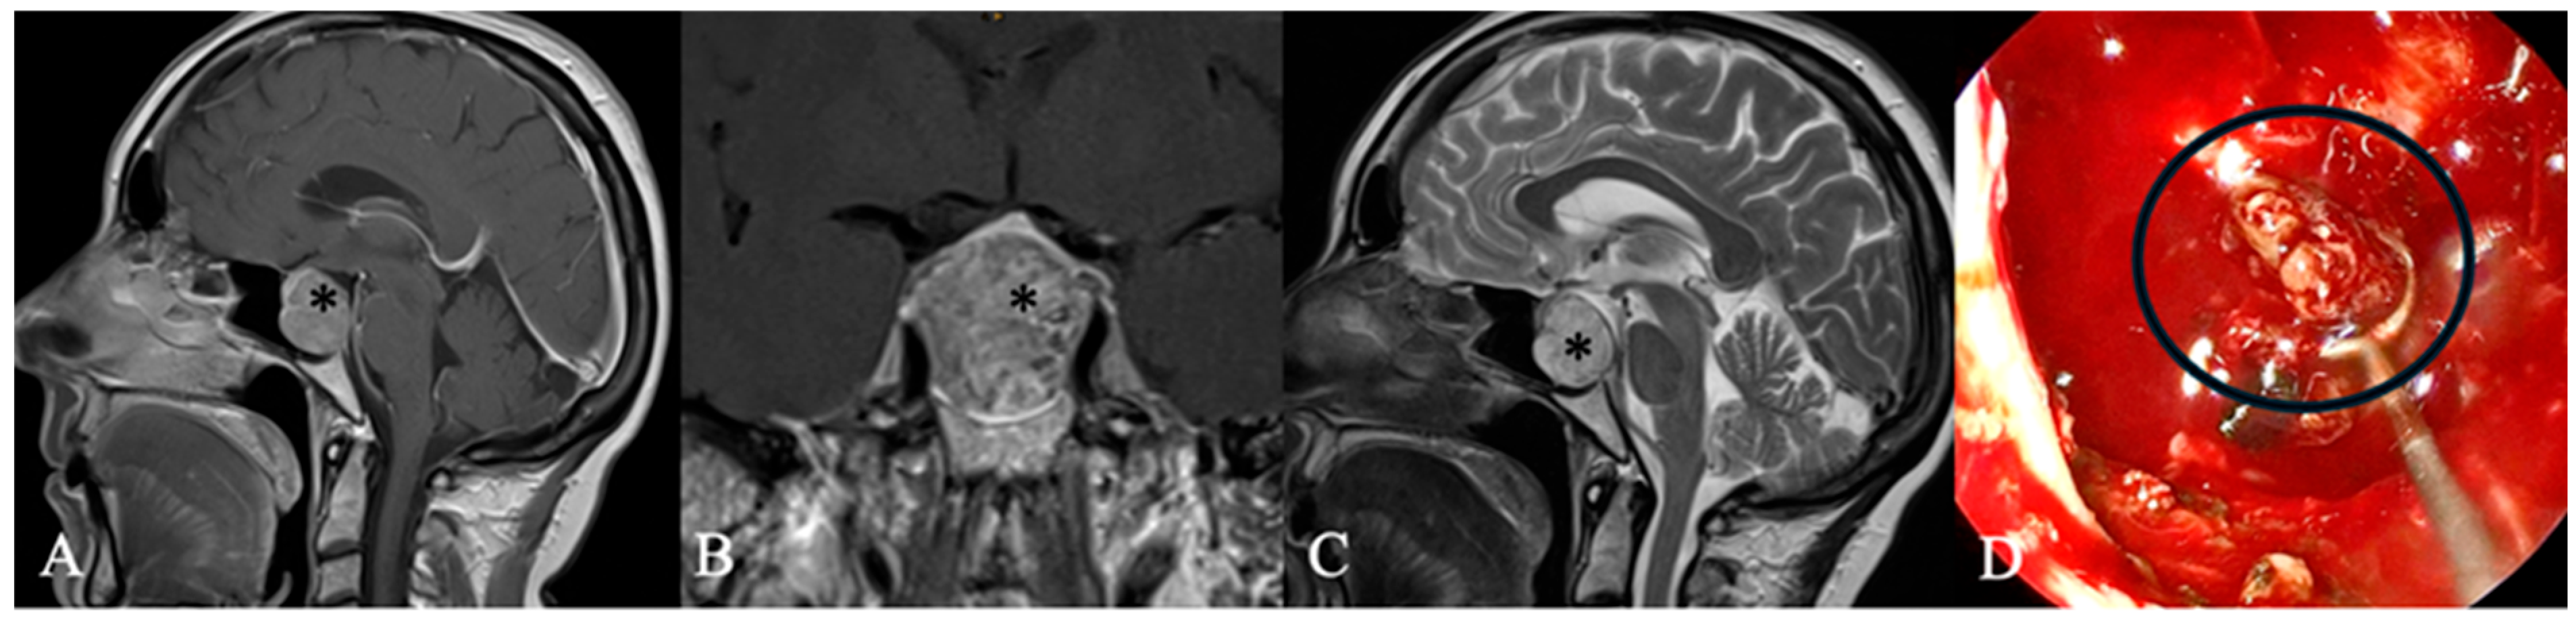

4.2. Differential Diagnoses and Case Presentations